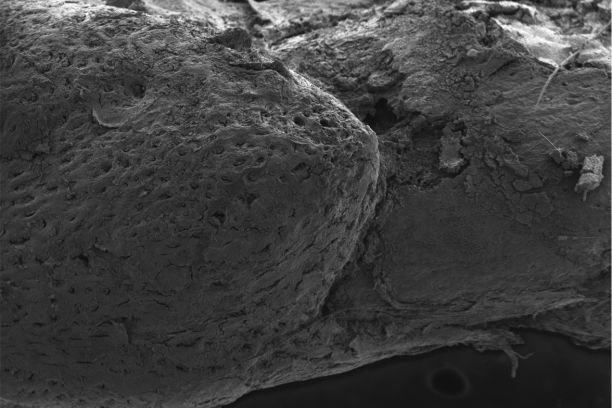

The Cassat Lab studies host-pathogen interactions during invasive bacterial infection, with a special emphasis on understanding how infection and inflammation perturb musculoskeletal cell biology. Osteomyelitis (bone infection) is one of the most common invasive bacterial infections in children, and it also occurs frequently in adults after trauma or surgery. The bacterial factors that promote survival in the bone, as well as the host factors that protect from osteomyelitis, are poorly defined. We have developed a variety of tools to understand how bacteria and inflammation trigger changes in bone biology, including a murine model of Staphylococcus aureus osteomyelitis, high-resolution 3D imaging of bone remodeling, and cell culture models of osteoblast and osteoclast proliferation and function.